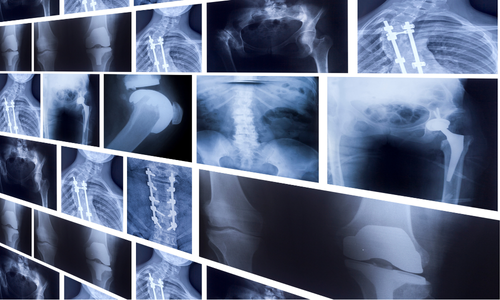

整形外科

肩・膝・腰などの関節や筋肉の痛み、スポーツによるケガなどを診療します。

レントゲン検査を行い、炎症や骨の状態を確認したうえで最適な治療を提案します。